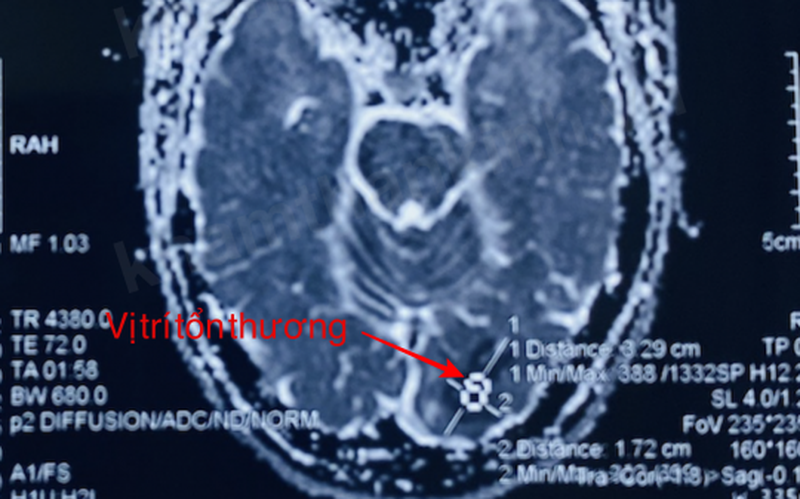

Bệnh nhân được đưa vào Bệnh viện Hữu nghị Việt Tiệp trong tình trạng thị lực mắt phải 8/10, soi đáy mắt và mắt trái bình thường, kết quả chụp cộng hưởng từ sọ não cho thấy hình ảnh nhồi máu não thùy chẩm bên trái.